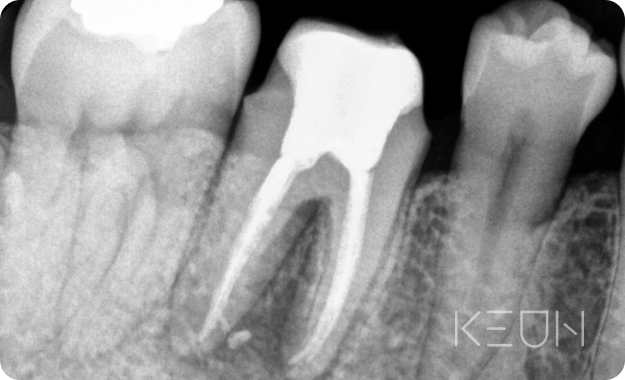

신경치료 전후사진.

- Before

- After

*모든 치료전/후 사진은 환자분의 동의하에 촬영 및 게시되었습니다.